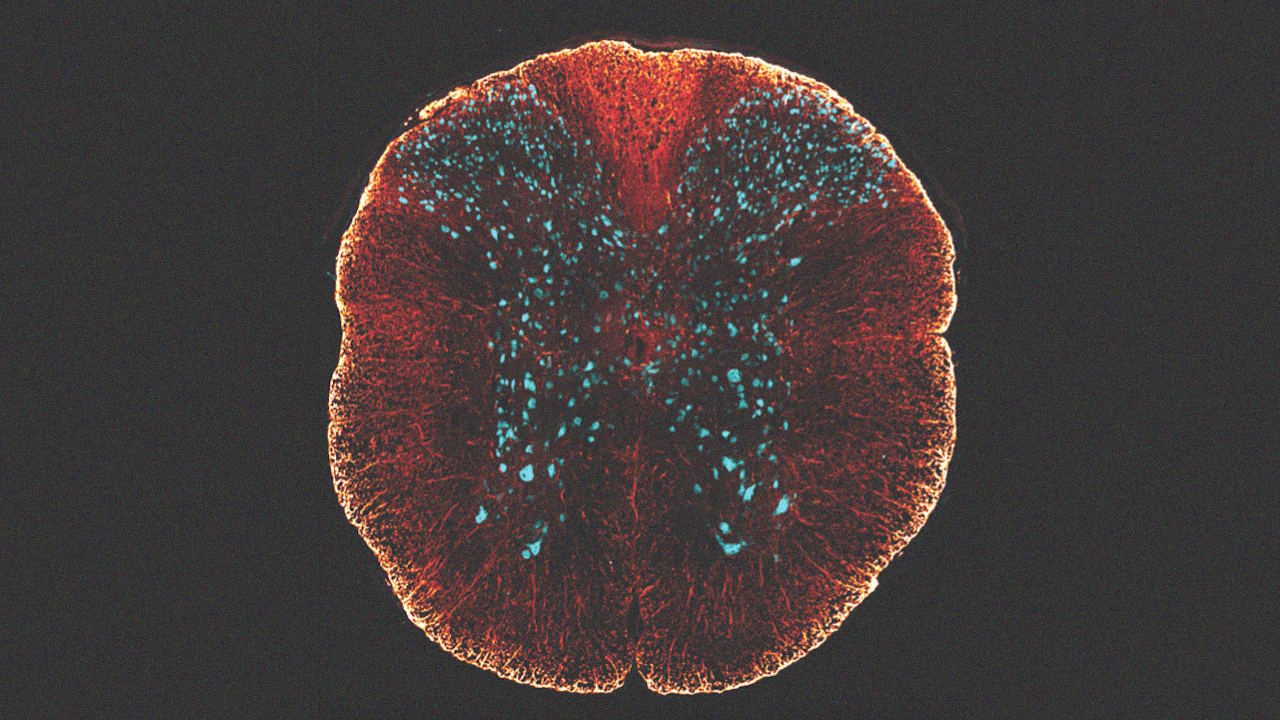

Зріз спинного мозку миші. Саме його нейрони уражаються через спінальну м'язову атрофію. Diogo Paramos-de-Carvalho